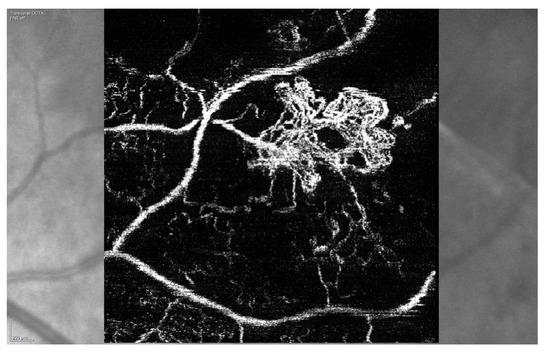

3.1. Radiation (Chorio)Retinopathy

3.2. Radiation Maculopathy

3.3. Radiation Optic Neuropathy